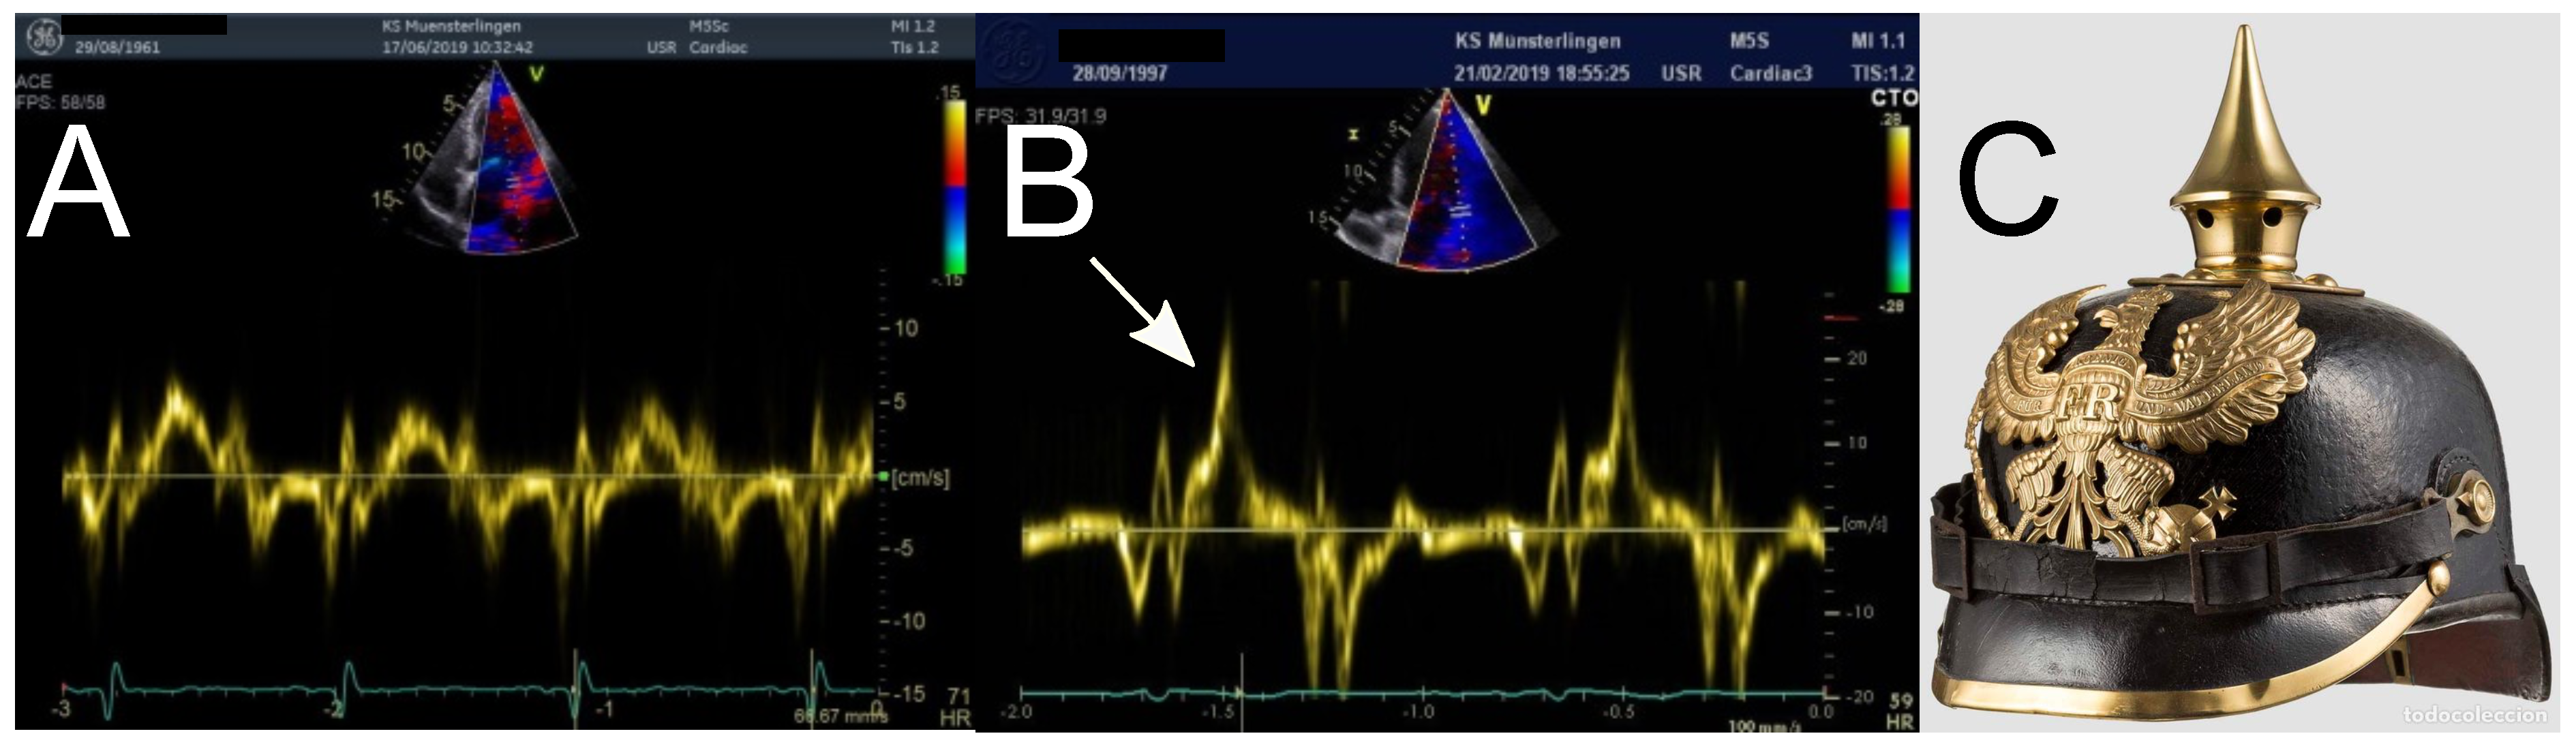

- Muthukumar, L.; Rahman, F.; Jan, M.F.; Shaikh, A.; Kalvin, L.; Dhala, A.; Jahangir, A.; Tajik, A.J. The pickelhaube sign: Novel echocardiographic risk marker for malignant mitral valve prolapse syndrome. JACC Cardiovasc. Imaging 2017, 10, 1078–1080. [Google Scholar] [CrossRef] [PubMed]